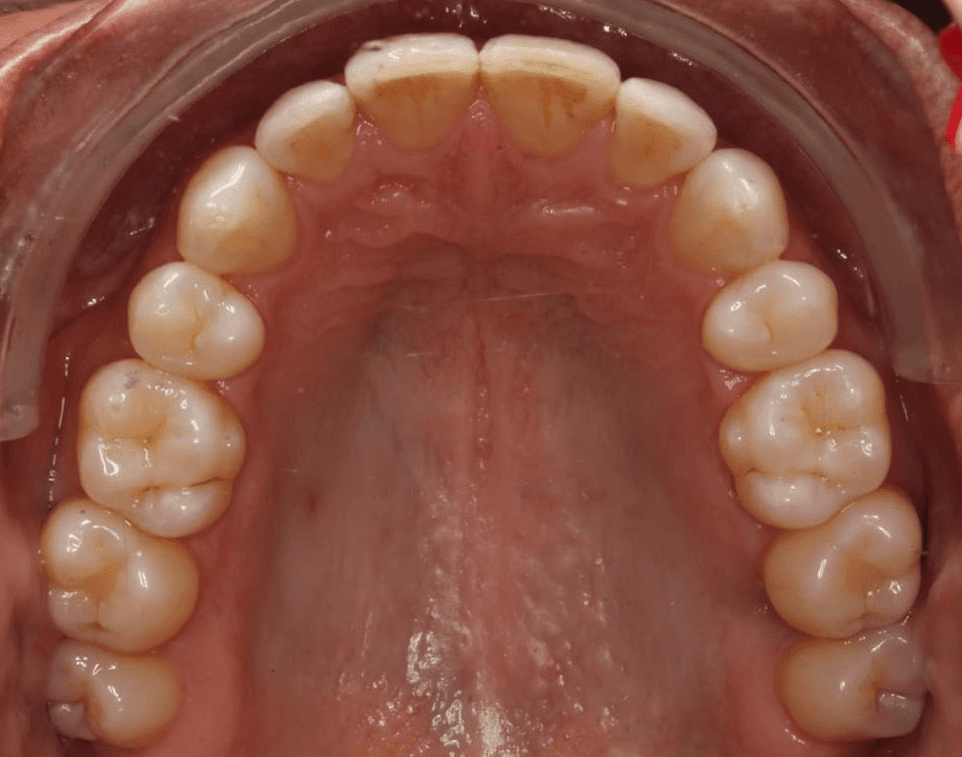

Diganosis: Minor and moderate crowding, anterior open bite, reverse smile arc, narrow maxilla, crossbite, tapered arch form

INTRAORAL